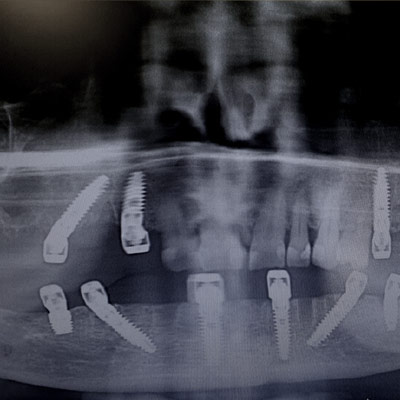

Full Arch Implant Rehabilitation

Questo corso ti prepara a gestire le riabilitazioni di una o entrambe le arcate su soli supporti implantari. Impariamo a gestire il paziente totalmente edentulo, parzialmente edentulo e quello con dentizione terminale.

All on x-procedures from A to Z.